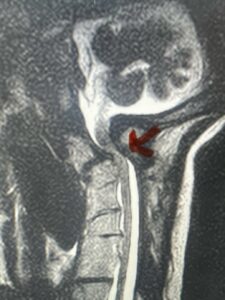

This is a 42 year-old female who presents with severe progressive weakness and numbness and difficulty with balance over a 6-month period. She has a history of having a motor vehicle accident at 5 years old but was never imaged. On exam she was noted to be severely myelopathic. Imaging revealed severe spinal cord compression at the level of C1 (Figs 4a and b).

Fig. 4a: Sagittal T2-weighted cervical MRI demonstrating severe cord compression with myelomalacia of upper cervical spinal cord (red arrow). Notice the increased atlanto-dens interval (red dot).

Cervical x-rays revealed a significantly increased atlanto-axial interval (Fig. 5) On review of her imaging studies it was noted that the right C2 isthmus was very thinned by the vertebral foramen (Figs 6a, b, and c) which would make an attempt at placing a C2 pars screw dangerous. A decision was made to perform an occipital-cervical fusion because only possible unilateral fixation and an extensive C1 laminectomy to be performed eliminating a fixation point if a more traditional C1-C2 was performed. Even if C1 lateral mass screws were able to be placed one could only perform a unilateral screw construct fixation to C2. We performed an occipital cervical fusion down to C4 to get enough inferior fixation and C1 laminectomy. The decompression went well. We placed a left unilateral pars screw and bilateral C3 and C4 lateral mass screws. We placed three 12 mm screws in the midline keel (Fig. 7). Postoperatively the patient had all around improvement in her symptoms and did not qualify for rehab. Her post op films at 6 weeks (Fig. 8)